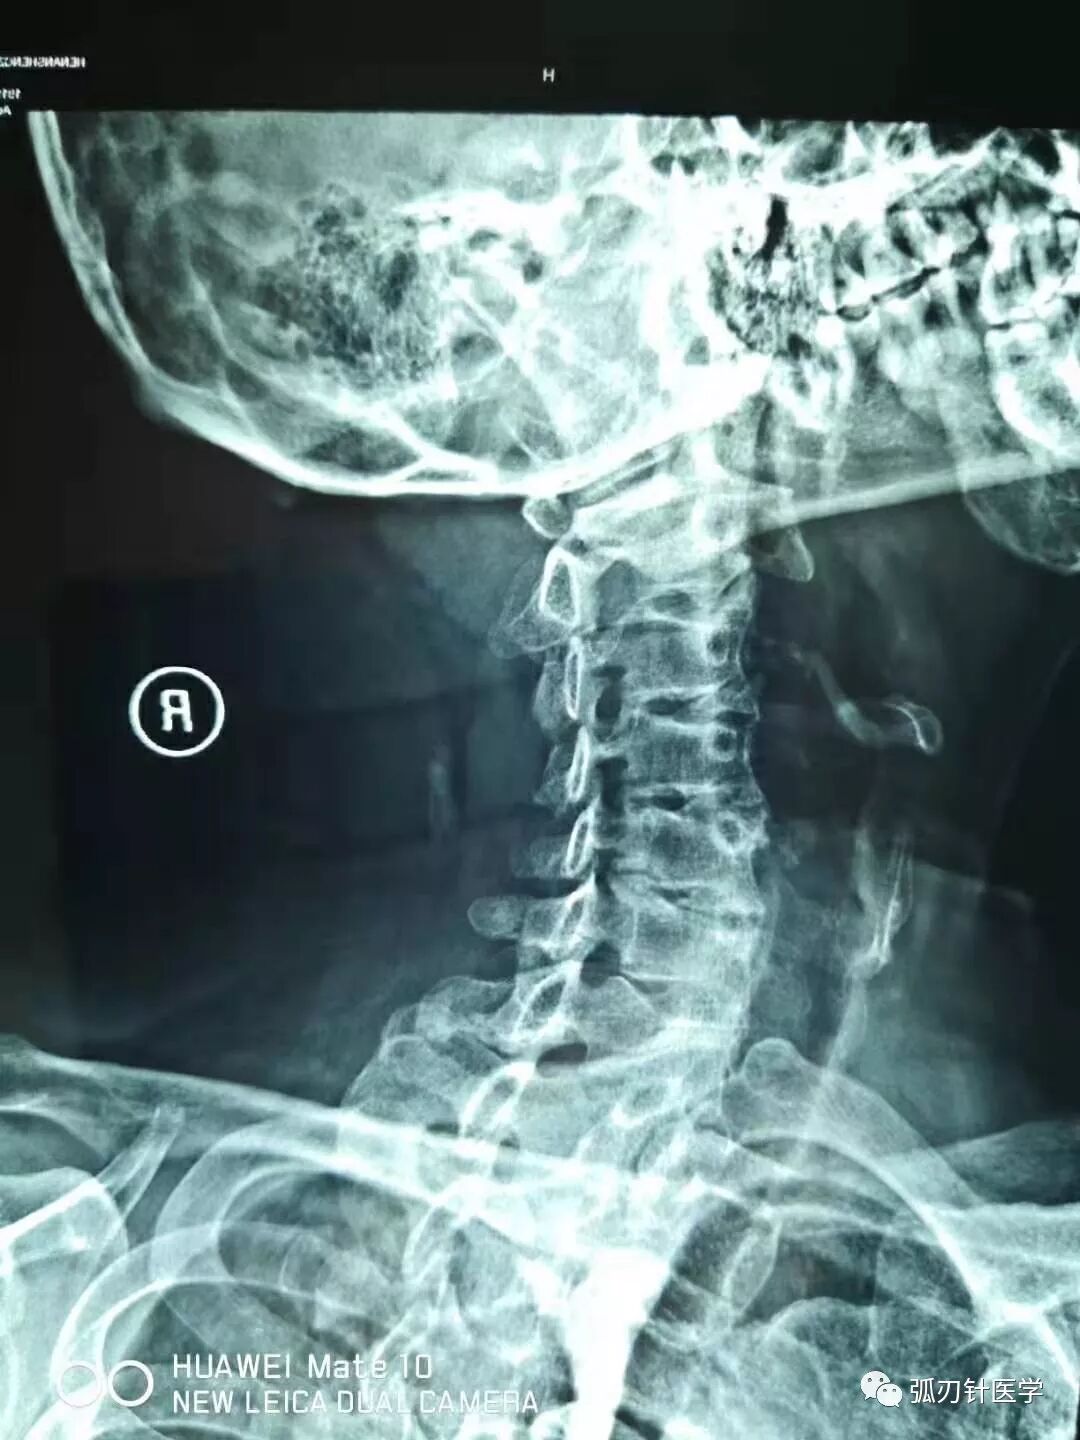

胳膊麻、脖子疼,一个中年男性患者典型的颈椎片和磁共振:骨质增生、项韧带钙化、椎间盘突出、椎间孔狭窄……